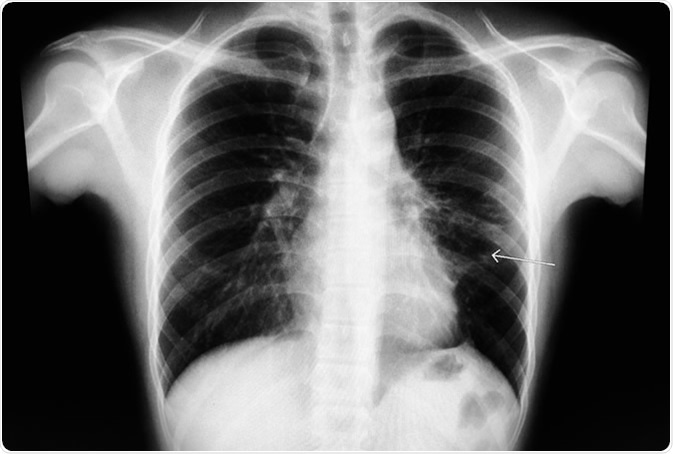

Chest X-ray known case S/P left anterior mediastinum mass. The study shows recticulo-fibrosis at medial perihilar LUL, and small tenting LLL basal fibrosis. Cardiac contour and rib cages are intact. Image Credit: Good Image Studio